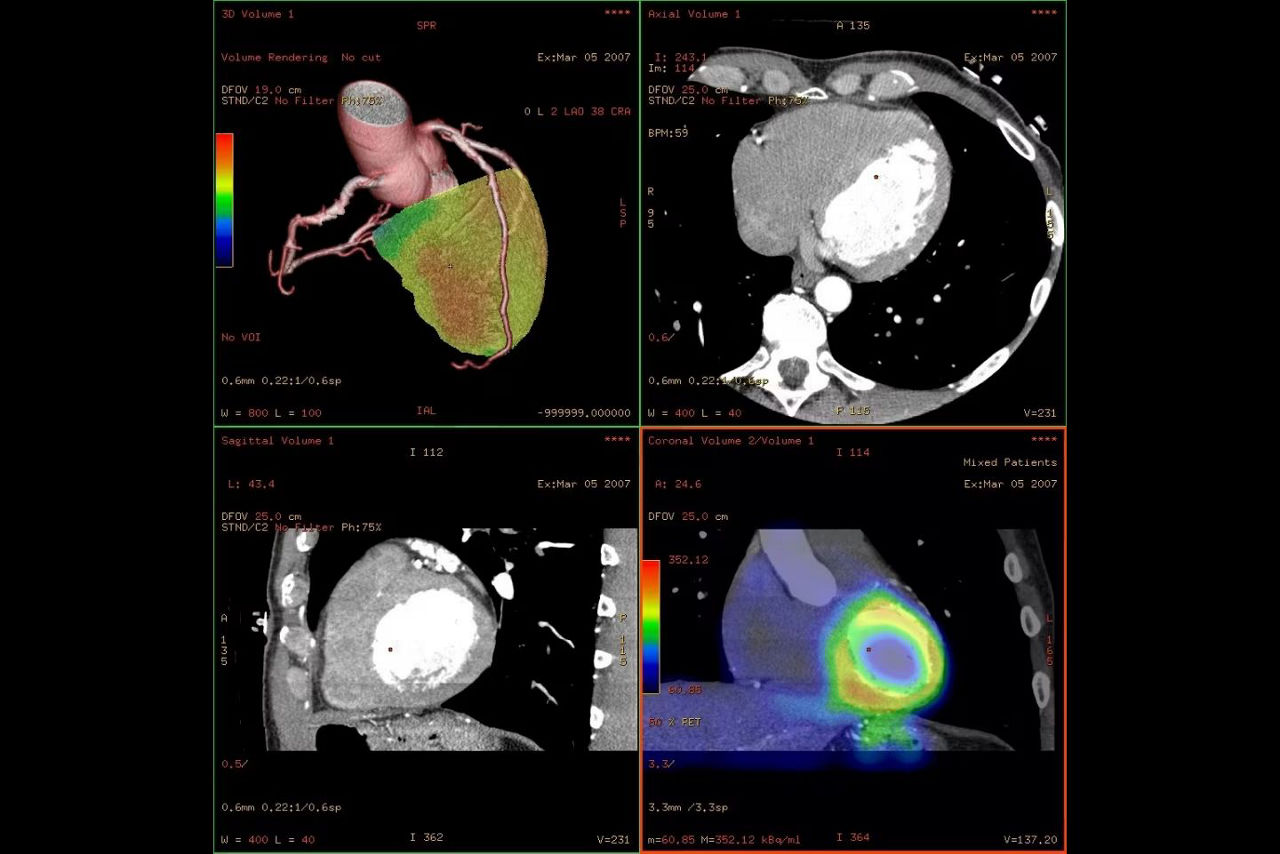

Fusion of cardiac physiological and anatomical information right before your eyes.

CardIQ Fusion* offers you 2D, 3D, or reformatted protocols to help you analyze and measure the extent of compromised coronary arteries. With CardIQ Fusion, you can visualize SPECT and PET physiological perfusion and viability data under stress and rest conditions. And it allows you to combine the anatomical and physiological data in fused 2D or 3D views.